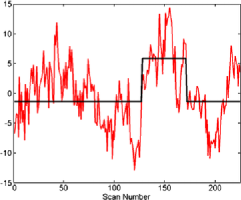

The subject in Figure 3 seems to exhibit strong deviations from stationarity—in fact, the -value associated with this subject is below based on the bootstrap test given in Section 7. It should be stressed that the change detection is a global hypothesis test combined over all components considered. In this way, while taking more components will help increase the chance that the change is present in one, it will come at the cost of the size of the change needed in finite samples for an omnibus test of this type. However, the subject shown in the figure did cause a rejection of the null hypothesis of no change both in the 64 and 125 subspace size omnibus tests. While the pictures in Figure 3 indicate that an epidemic change is indeed a good first approximation for the nonstationarities occurring for this particular subject, more deviation (maybe more change-points) does seem to be present. In Figure 4, a second subject is shown with a much smaller deviation from stationarity (most of the components seem to have little to no possible mean change present), which is significant but does not survive the false discovery rate (FDR) correction (see Section 4.3).

Figures 5–7 show three component time series selected for their different properties. The component in Figure 5 can be seen to be a candidate series for a change to have occurred with the resulting change corrected series visually appearing much more stationary (although it is likely there are other nonstationarities present as well). This series, from subject 01018 in the connectome data set, was found to have evidence of nonstationarities when the sample version of the statistic (given in Section 6.2) was tested on both a 64 and 125 component projection.

When testing subject 48501 from the connectome data, from whom the components can be seen in Figure 4, an epidemic change seems to be quite a good model for several components, but only a small part of the time series deviates from stationarity. For example, component 7 in Figure 6 shows a less pronounced but still plausible epidemic change compared with component 23 of subject 01018 in Figure 5. However, as can be seen in another component (Figure 7) from subject 48501, some of the components seem to be stationary without any change present.

Given that nearly 200 subjects were tested, a multiple comparison correction was implemented using the independent FDR method by Benjamini and Hochberg (1995). The use of an independent FDR is based on the fact that the comparisons are being taken across subjects who can be assumed to be independent of each other. Subject 01018 (Figure 3) survived the FDR correction and evidence was still found of nonstationarities being present. Subject 48501, whose projections are seen in Figure 4, also rejected the null hypothesis but only at about a 3% level, hence not surviving the FDR correction.